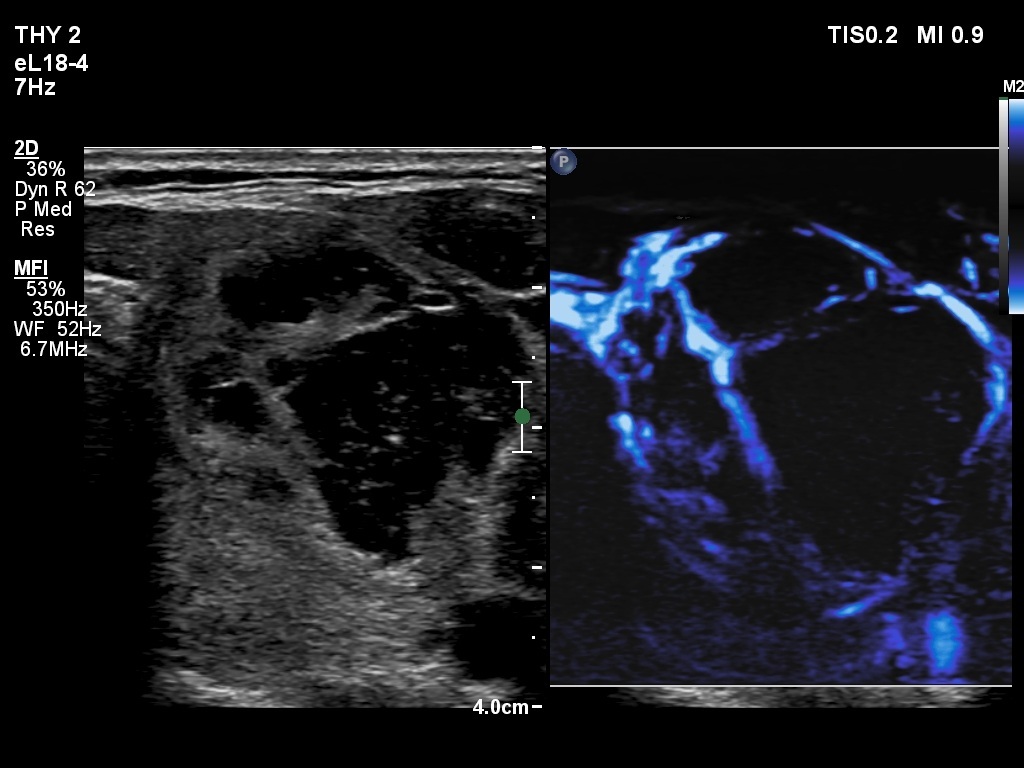

Ultrasonography. The thyroid was echonormal. The right lobe contained several discrete areas without any clinical significance. There was multi-chambered cystic nodule in the left lobe. The nodule had echonormal solid part and presented halo sign.

- The distinction between a multi-chambered cyst and a spongiform cyst is important, because in the latter the risk of malignancy is practically zero. In spongiform cysts almost the entire nodule is composed of cystic areas, and there is very small proportion of solid areas.

- The cyst has just started refilling after the evacuation.